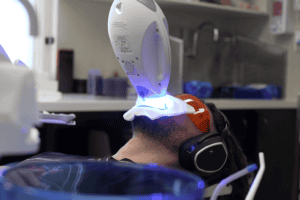

A bright, white smile is something many of us strive for, but teeth can naturally discolour over time. This can be due to age, lifestyle